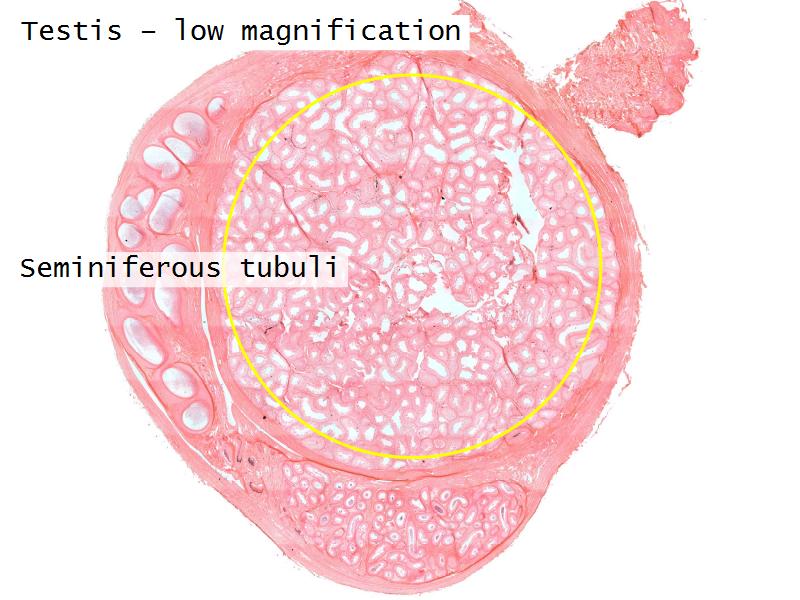

- Testis

- C2: Testis

- C2: Testis = testosterone

- D1: Leydig cells

- D1: Leydig cells = testosterone

- Slide 84: Testis